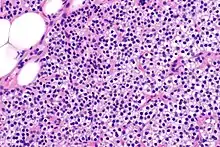

Parathyroid glands are normally composed of chief cells, adipocytes and scattered oxyphil cells.[27][14] Chief cells are thought to be responsible for the production, storage and secretion of parathyroid hormone. These cells appear light and dark with a prominent Golgi body and endoplasmic reticulum. In electron micrographs, secretory vesicles can be seen in and around the Golgi and at the cell membrane. These cells also contain prominent cytoplasmic adipose.[27][14] Upon onset of hyperplasia these cells are described as having a nodular pattern with enlargement of protein synthesis machinery such as the endoplasmic reticulum and Golgi. Increased secretory vesicles are seen and decreased intercellular fat is characteristic.[27][24] Oxyphil cells also appear hyperplasic however, these cells are much less prominent.

Biochemically, there are changes in function between normal and nodular hyperplastic parathyroid glands. These changes involve proto-oncogene expression and activation of proliferative pathways while inactivating apoptotic pathways.[28] In nodular parathyroid tissue increased expression of TGF-a, a growth factor, and EGFR, its receptor, results in aggressive proliferation and further downregulation of vitamin D receptors, which act to suppress hormone secretions.[25][8][28] Furthermore, the proliferative marker, Ki67 is seen to be highly expressed in the secondary nodular hyperplastic state.[28][25] Tumour suppressor genes have also been highlighted as being silenced or degraded in nodular hyperplastic parathyroid tissue.[8][28] One such gene, p53, has been shown to regulate multiple tumour suppressor pathways and in tumorigenesis can be degraded by b-catenin. This pathway, in some aspect, is mediated by CACYBP, which is highly expressed in nodular parathyroid hyperplasia.[28]